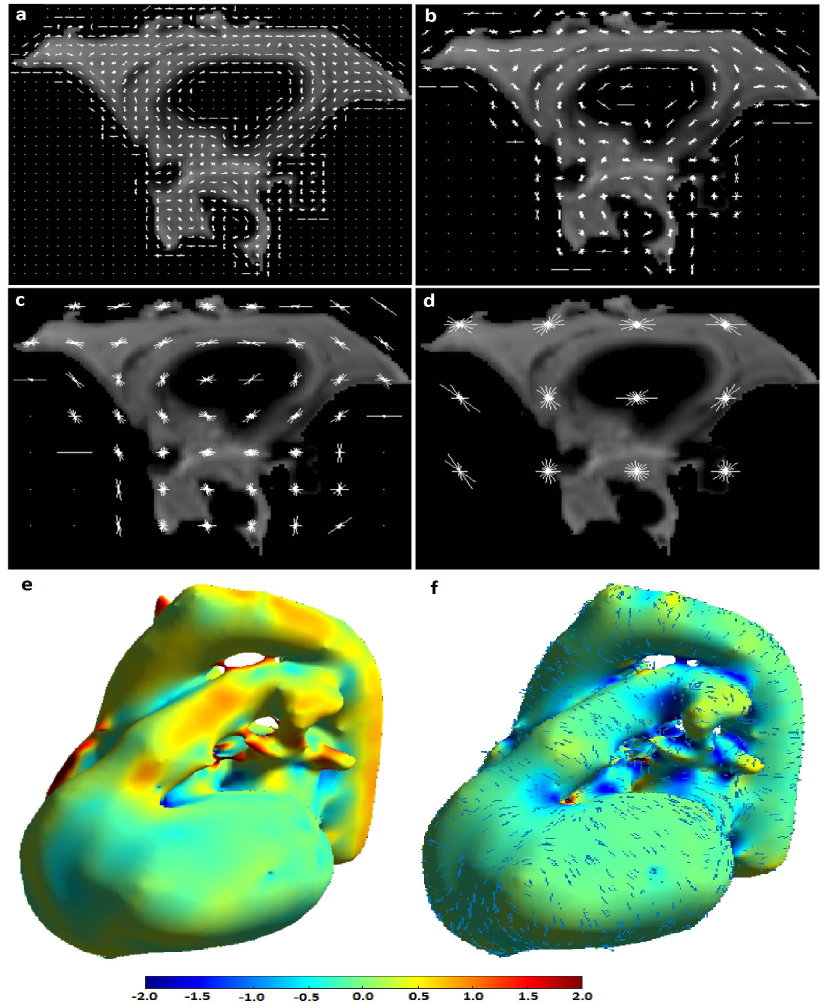

The classification priors of the samples could be estimated by any method such as the multiatlas registration or the hierarchical random forest classifier proposed in [Fallah 2018a, Fallah 2018b, Fallah 2019b, Fallah 2019a]. This happened when the classification probabilities estimated by those methods were not accurate enough to be considered as final classification probabilities (posteriors) rather as initial classification probabilities (priors). For example, the classification probabilities estimated by the proposed forest could not differentiate different kinds of cardiac adipose tissues on fat-water MR images. They could only differentiate the overall adipose tissues from nonadipose tissues. This was due to lack of spatial information in the forest, similar contrasts and features of the cardiac adipose tissues, and weak boundaries between them. The cardiac adipose tissues were spatially close to each other and separated only through thin septa which were hardly detectable under spatial resolution of standard clinical scanners at 3 T. Figure 1 shows voxelwise classification probabilities estimated by the proposed forest for the cardiac adipose tissues and the resulting segmentations on various slices of a fat image. Figure 2 shows overall segmentations of the cardiac adipose tissues based on the voxelwise classification probabilities estimated by the proposed forest on some axial slices of a fat image. Despite inaccuracies of the priors, they, features, and the spatial (neighborhood) relationships of the samples could pave the way for another classifier such as the neighborhood graph to classify the samples more accurately. For example, the priors could approximately localize an addressed object in an image and thereby speed up or reduce the complexity of its accurate segmentation. The more accurate classification probabilities were called the posteriors. Accordingly, the neighborhood graph was supposed to estimate the classification posteriors of every sample (vertex) with regard to its features, its priors, and its spatial (neighborhood) relationships with other samples of the same resolution .

The graphs proposed in section 3 and section 4 tried to implicitly or explicitly detect boundaries between different classes (e.g. objects) in spatial domain (e.g. image). The implicit boundary detection used the Tukey’s function of the features differences of the connected samples and the explicit boundary detection applied a 3D Sobel operator to each intensity channel of the samples. Both of these techniques could enhance the accuracies of a classification in spatial domain. However, their performance was limited when the features of different classes were similar or the boundaries were too weak to be detected. An example of these cases was segmentation of cardiac adipose tissues on fat-water MR images. As shown in Figure 1 and Figure 2 the random forest classifier proposed in [Fallah 2018a, Fallah 2018b, Fallah 2019b, Fallah 2019a] could only detect the overall adipose tissues but could not differentiate different kinds of it. The neighborhood graph proposed in section 3 or section 4 took the priors, the features, and the classification reliabilities of the samples and applied an implicit or explicit boundary detection. This could enhance the accuracy of the segmentation of the cardiac adipose tissues on fat-water MR images but the performance was still unsatisfactory. Figure 7 shows the voxelwise classification posteriors estimated for these adipose tissues by the implicit and/or explicit boundary detection on two axial slices of a fat image. To tackle features similarities and undetectable boundaries between different classes in spatial domain, we further extended the spatial feature-based subgraph by guiding the classification through additional information. These information got encoded into a diffusion-based susceptible-infected-recovered (SIR) model proposed in [Bampis 2017].

Figure 8 shows color-coded curvatures and directions of normals and minimum and maximum curvatures of the surface of a cardiac structure segmented over a volumetric water image. Among the introduced curvatures, the maximum curvature had the maximum variance and could thereby capture most of the shape variations over a surface.